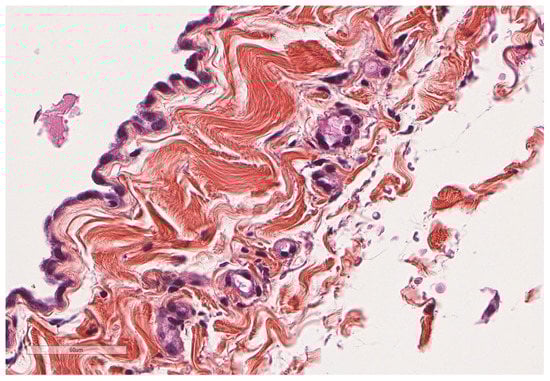

- Karpathiou, G.; Hathroubi, S.; Patoir, A.; Tiffet, O.; Casteillo, F.; Brun, C.; Forest, F.; Rahman, N.M.; Peoc’h, M.; Froudarakis, M.E. Non-specific pleuritis: Pathological patterns in benign pleuritis. Pathology 2019, 51, 405–411. [Google Scholar] [CrossRef] [PubMed]